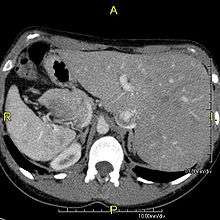

The condition affects all major structures within the thorax and abdomen. Generally, the organs are simply transposed through the sagittal plane. The heart is located on the right side of the thorax, the stomach and spleen on the right side of the abdomen and the liver and gall bladder on the left side. The heart's normal right atrium occurs on the left, and the left atrium is on the right. The lung anatomy is reversed and the left lung has 3 lobes while the right lung has 2 lobes. The intestines and other internal structures are also reversed from the normal, and the blood vessels, nerves, and lymphatics are also transposed.

Situs inversus is found in about 0.01% of the population, or about 1 person in 10,000. In the most common situation, situs inversus totalis, it involves complete transposition (right to left reversal) of all of the abdominal organs. The heart is not in its usual position in the left chest, but is on the right, a condition known as dextrocardia (literally, right-hearted). Because the relationship between the organs is not changed, most people with situs inversus have no medical symptoms or complications, although they should wear a medical identification tag to warn emergency medical staff that the patient's internal organs are reversed from normal so they can act accordingly, e.g. by listening for a heartbeat on the right rather than left side of the chest.[1]

In rarer cases such as situs ambiguus or heterotaxy, situs cannot be determined. In these patients, the liver may be midline, the spleen absent or multiple, and the bowel malrotated. Often, structures are duplicated or absent altogether. This is more likely to cause medical problems than situs inversus totalis.[2]